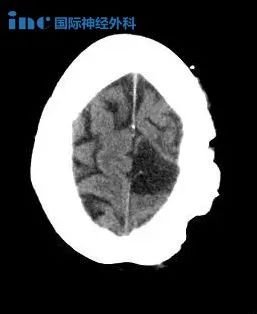

AVM的診斷是通過計算機斷層掃描(CT)、磁共振成像(MRI)和腦血管造影,其中包括x射線(x射線)成像,然后注射造影劑。簡單地說,造影劑被注射到一根導管中,導管插入病人的股動脈,然后通過頸內(nèi)動脈到達大腦。拍攝的影像顯示了AVM的局部位置。這些影像學檢查很重要,因為除了顯示AVM的位置外,它們還可以用來確定AVM的原始大小、治療后的大小變化,以及AVM是否出血或未破裂。通常,AVM 病灶的評估是通過一種名為Spetzler-Martin (SM)分級量表的評分方法進行的,該方法有助于評估手術(shù)死亡風險和嚴重不良反應(SAEs)。SM分級量表考慮到了: